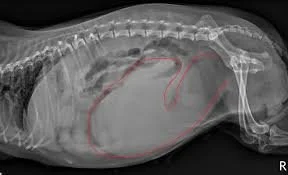

X-ray of dogs abdomen

Closed pyometra can cause the uterus to rupture, spilling infection into the abdomen. This leads to septic shock and death if not treated immediately.

xray pyometra

X‑rays

An enlarged, fluid‑filled uterus may be visible.